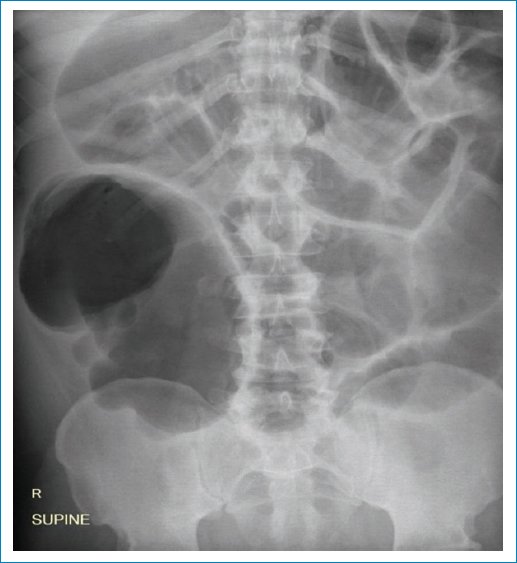

Figura 2. (A) Embrión humano de 8-9 semanas de gestación (imagen tomada de Wikimedia Commons, usuario Anatomist90, disponible en: https://commons.wikimedia.org/wiki/File:Human_embryo.jpg, bajo licencia CC BY-SA 4.0, con autorización). (B) TC abdominal con reconstrucción en plano coronal de paciente masculino de 67 años que acude a nuestra institución con dolor en fosa ilíaca derecha de 4 horas de evolución, sin otros síntomas acompañantes. Se evidencia al ciego distendido y volvulado con punto de torsión en válvula ileocecal (flecha blanca), e incipientes signos de neumatosis parietal.

Figura 3. Scout de TC abdominal del mismo paciente de la figura 2. Si bien el signo puede observarse en cualquier cuadrante abdominal, es importante distinguir la concavidad derecha del vólvulo junto con su segmentación haustral.